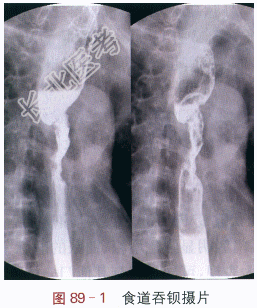

影像学资料如图89-1~图89-2所示。

读片分析:食道吞钡摄片见食道中段管腔明显狭窄、管壁不规则,可见黏膜破坏,钡剂通过变慢,上段食道扩张;增强CT扫描显示食道中段局限性管壁不规则增厚、强化较明显,上方食道扩张。结合患者临床表现,考虑食道中段癌可能。